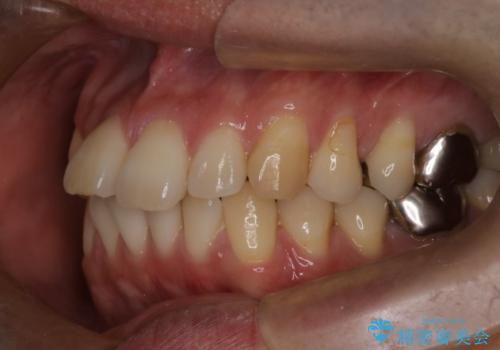

- 前歯の出ているのが気になる、下唇を噛んで痛いとのことで来院された患者様です。マウスピース矯正をご希望でした。

奥歯の噛み合わせはしっかりしていましたので、奥歯の動きは最小限にし、前歯の並びに集中した治療計画+インビザラインのシミュレーションを作成しました。

奥歯の噛み合わせは整っていたため、前歯の並びを美しく修正することに専念できました。マウスピース矯正による治療で短期間で改善しました。